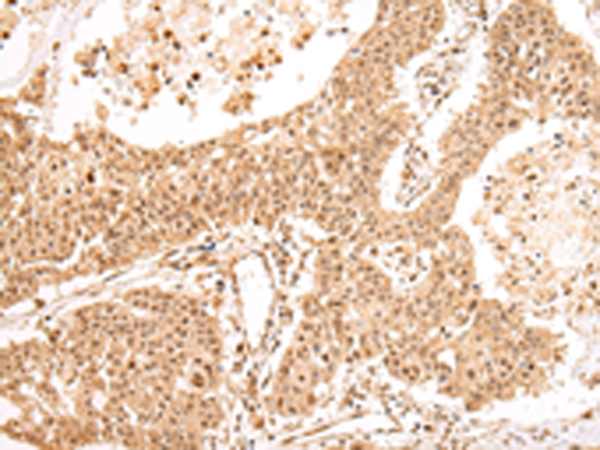

分类: 科研抗体货号: P08955别名: UEF; FCHL; MLTF; FCHL1; MLTFI; HYPLIP1; bHLHb11应用: IHC反应种属: Human, Mouse